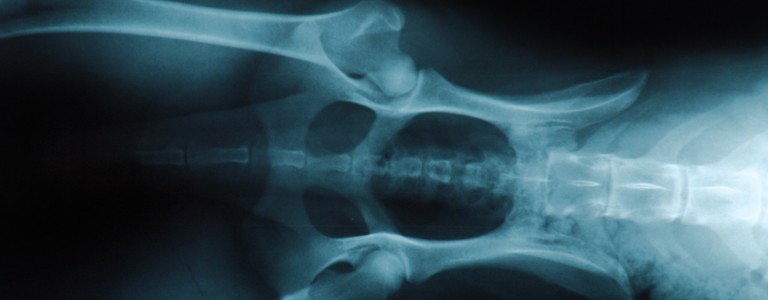

Si vous suspectez que votre chien souffre d'arthrose, un vétérinaire pourra en confirmer le diagnostic grâce à votre description des symptômes, un examen clinique complet et des examens d’imagerie.